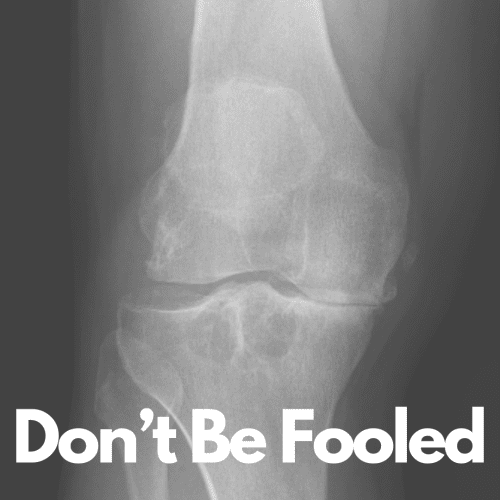

DON’T BE FOOLED The Truth About “Miracle Cures” and What Really Supports a Knee with Osteoarthritis Look at that X-ray. That’s not just a knee—it’s your reality or the future you’re trying desperately to avoid. Medial compartment osteoarthritis isn’t subtle. It grinds away at your freedom, step by step, until walking across the room feels […]